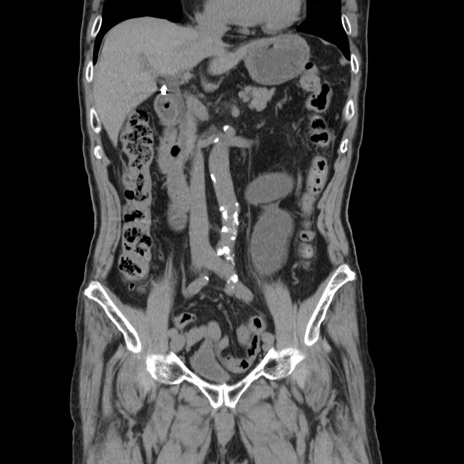

症例24(冠状断像)

【症例】80歳代男性

【主訴】左側腹部痛、嘔吐

【現病歴】本日早朝より左腹部に痛みあり。昼頃嘔吐認めたため、救急要請。

【既往歴】直腸癌(Mile手術)、胆摘

【身体所見】意識清明、BT 35.9℃、BP 221/93mmHg、SpO2 97%(RA) 、腹部:左ストーマ周囲に限局性の腹部膨隆あり。 膨隆部自発痛・圧痛あり・軟。

【データ】WBC 7700、CRP 0.09